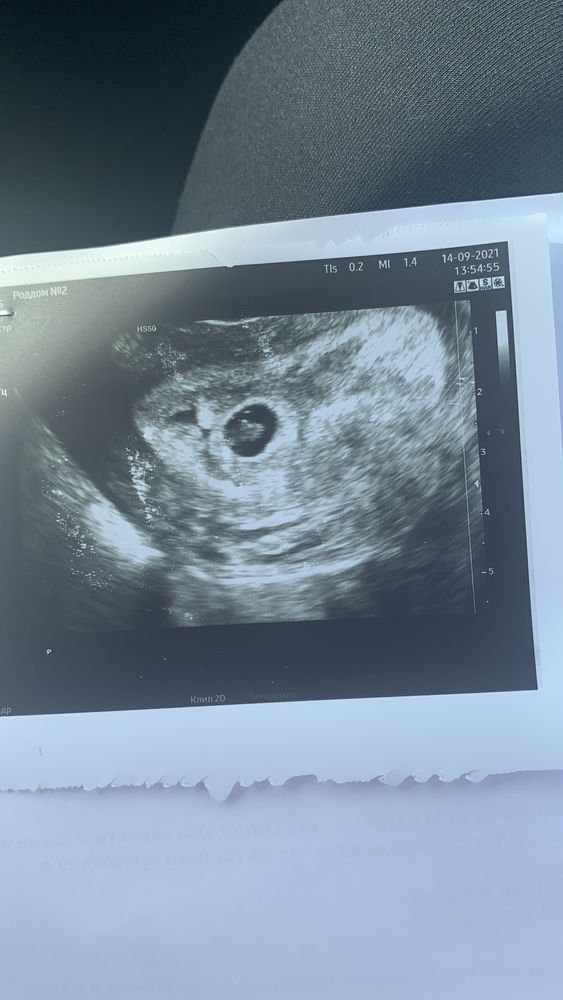

вот и поставили неразвивающуюся беременность.

вчера был срок 7+1 акушерских.

была на сроке 6 недель на узи в другой клинике, сказали просто, что сердцебиение есть. Не слушали ничего.

вчера делала плановое в мать и дитя, сказали, что сердцебиения не видят, надо убирать. Предложили подождать ещё три дня.

ктр 3,5 мм, ЖМ 5,6 мм. Эмбрион есть.